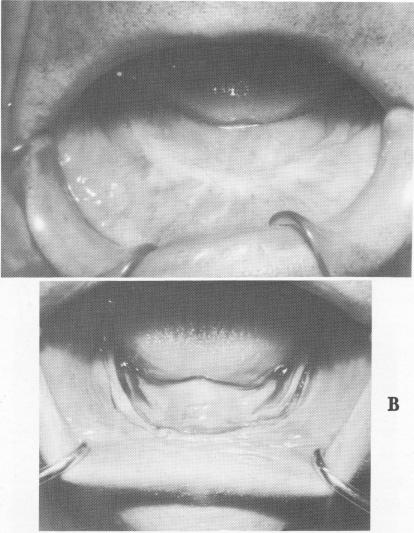

Fig. 12-10. A, The resorbed edentulous mandible just prior to the first surgical stage incision. Note how flat the ridge is when covered by the soft tissue. B, An incision was made along the crest of the soft tissue ridge directly down to the bone. It extended close to the retromolar pad areas on both sides.

A

4 Resorbed edentulous mandible prior to first surgical stage incision